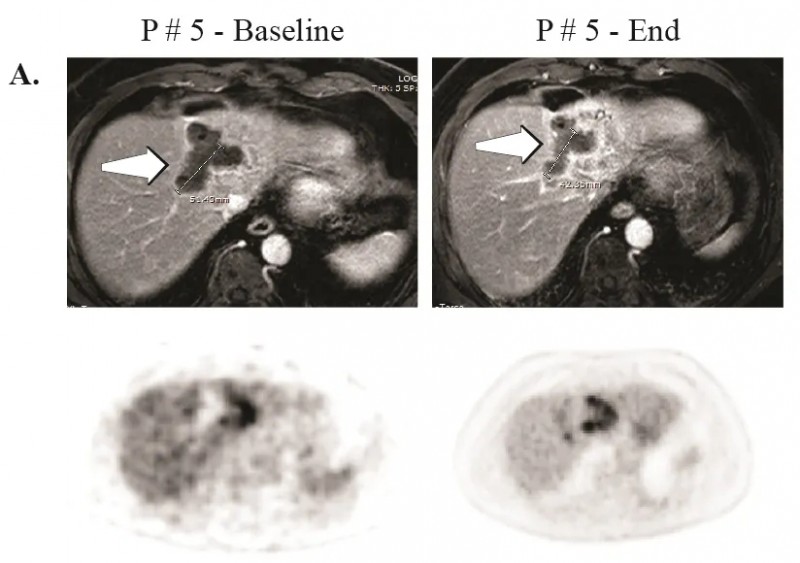

其中1例患者(5号患者)在CAR-T肝动脉输注治疗后23个月(102周)仍存活且病情稳定,该患者在试验结束后,对残留的无法切除肿瘤进行了微波消融治疗。该患者经MRI和PET检查显示病情稳定(SD)(详见下图A,箭头)。

▲图源“Clin Cancer Res”,版权归原作者所有,如无意中侵犯了知识产权,请联系我们删除